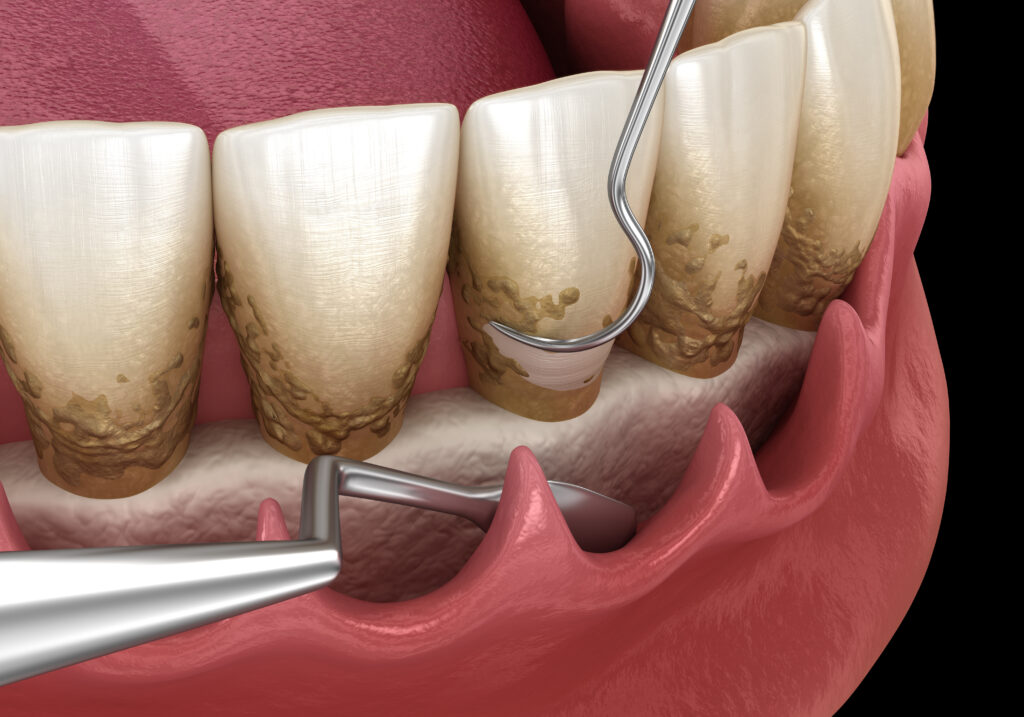

- Po stwierdzeniu choroby przyzębia (wynik CPITN > 2) kwalifikujemy pacjenta do poddziąsłowego skalingu i kiretażu w znieczuleniu miejscowym.

- Postępujemy wg protokołu FDM (full mouth desinfection)

- Pacjentów z zaawansowaną chorobą przyzębia przygotowujemy chirurgicznego kiretażu otwartego.